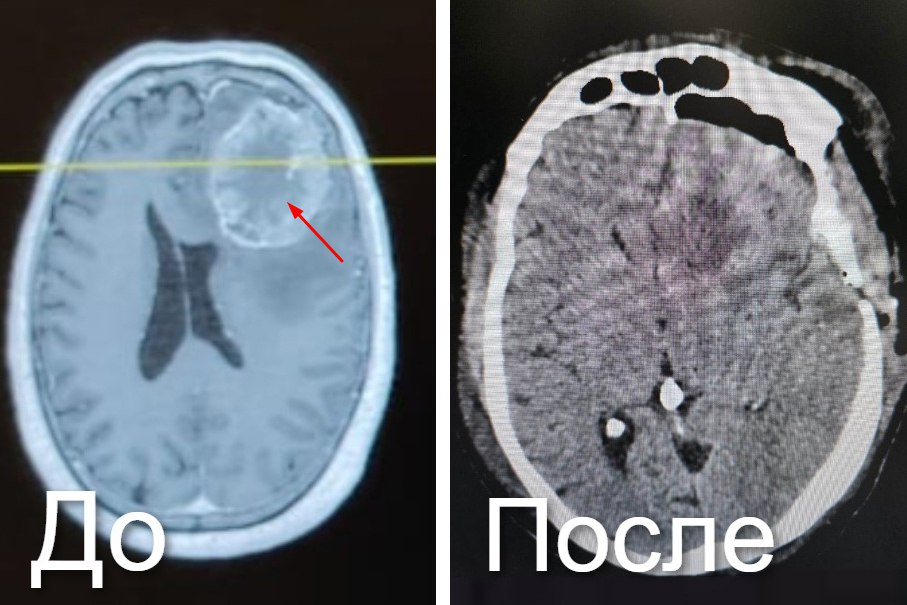

Спасли пациента с крупной опухолью мозга в Новокузнецке

Образование появилось от метастаз рака прямой кишки. С 2019 года выросло больше куриного яйца. Вызывало боль, тошноту, потерю координации.

Врачи провели ювелирную операцию. Ушло 5,5 часов. Использовали хирургический микроскоп и нейронавигационную систему.